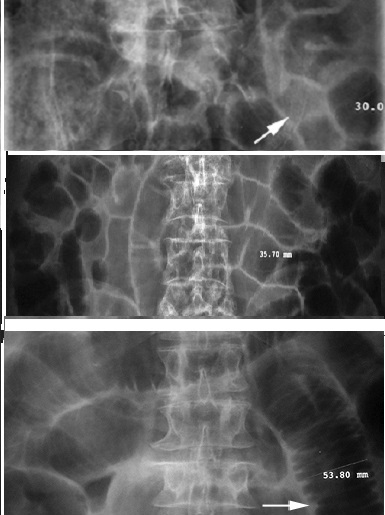

- Le grele du jeune enfant contient toujour d'air mais

le grele de aldulte ne contient pas ou tres peu . .Situe

au centre de l'abdomen et en circle par des plies

muqueuses et il peut efface en distendue . Sa

diametre peut atteint 30mm |

Aspect de l'intestin

grele normale ,en distention aerique legere et

inportant . Cliche ASP de face |